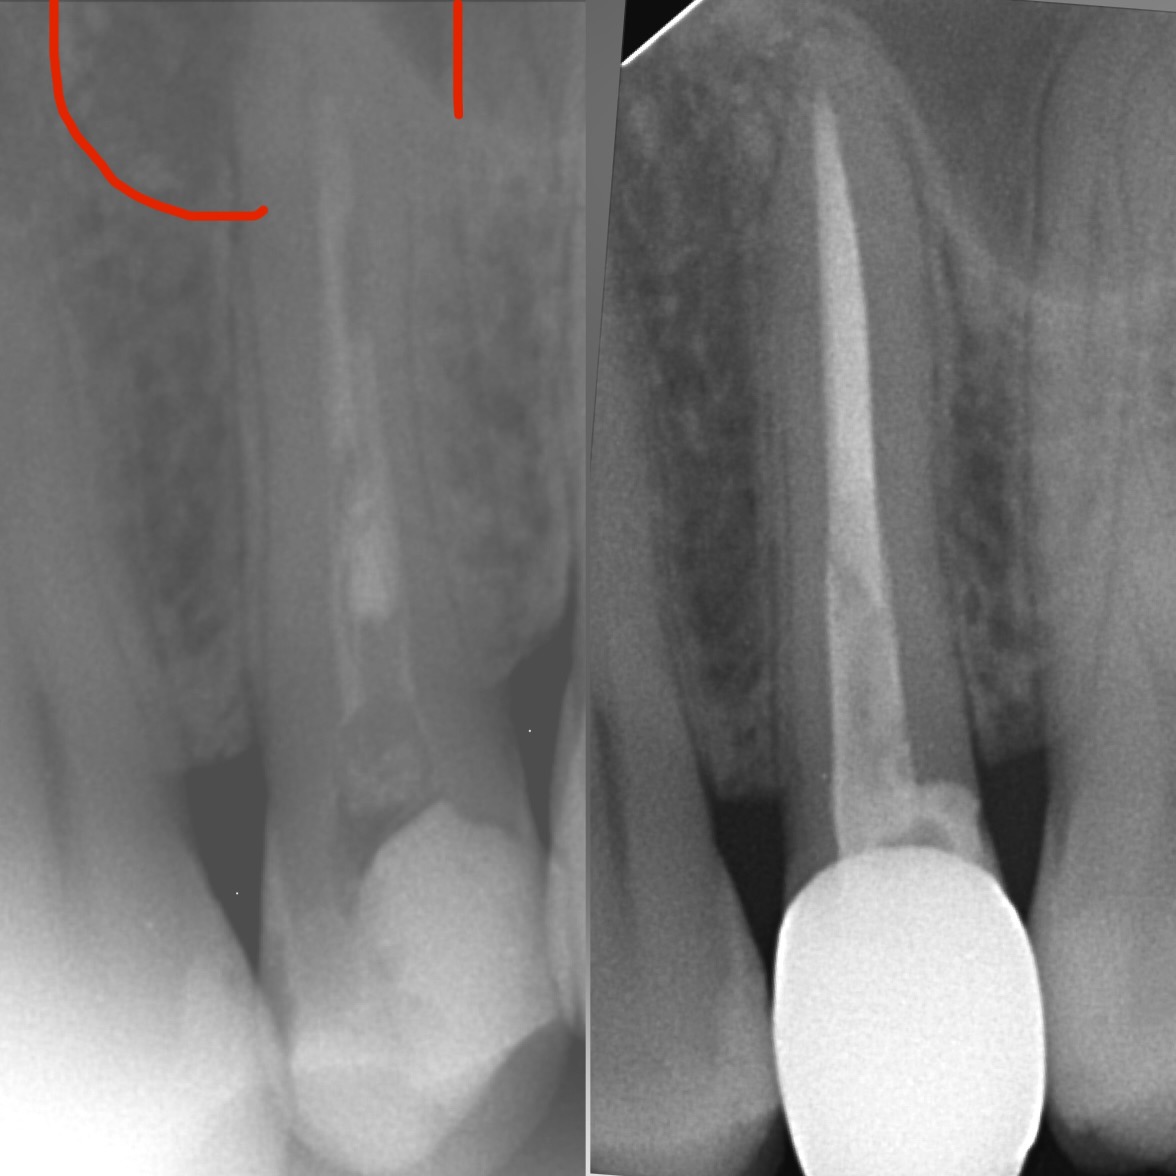

• Диагностика и лечение кариеса и его осложнений (пульпиты, периодонтиты)

• Эндодонтическое лечение корневых каналов с использованием стоматологического микроскопа